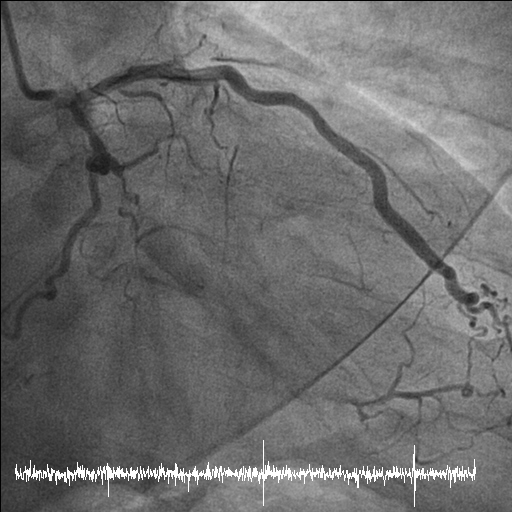

Coronary angiography disclosed orifice total occlusion with TIMI grade 0 antegrade flow at LAD, middle total occlusion at LCX, and RCA proximal total occlusion with auto-collateral to RCA distal.

Stage PCI for stumpless LAD-os-P CTO was arranged two months later. Antegrade strategy was tried initially, but shifted to retrograde approach due to wiring failed because of tiny LAD-M true lumen. We used SAL 1x6F guide via right femoral access. After trying, one septal collateral via PDA could be wired with a Fielder XT-R and Caravel. After switching the Caravel to Corsair Pro XS, it could be advanced to LAD-M. The CTO segment was retrogradely attempted with Conquest Pro, UB and finally reached LM body. Using a Sion blue, the wire could go into the antegrade guide, followed by advancing the Corsair Pro XS into the guide. The lesions were antegradely dilated with BC after RG 3 wire externalization and antegrade flow was established. By using a Crusade, the LAD proper could be successfully wired wtih a Fielder XT-A. LAD-M-D and LAD-os-P-M were predilated with a 2x30mm BC(IVUS confirmed all true lumen wiring) and respectively scaffolded with a 2.75x38mm Onyx and a 3x48mm Synergy. There was no residual stenosis over all 3 vessels.

Stage PCI for stumpless LAD-os-P CTO was arranged two months later. Antegrade strategy was tried initially, but shifted to retrograde approach due to wiring failed because of tiny LAD-M true lumen. We used SAL 1x6F guide via right femoral access. After trying, one septal collateral via PDA could be wired with a Fielder XT-R and Caravel. After switching the Caravel to Corsair Pro XS, it could be advanced to LAD-M. The CTO segment was retrogradely attempted with Conquest Pro, UB and finally reached LM body. Using a Sion blue, the wire could go into the antegrade guide, followed by advancing the Corsair Pro XS into the guide. The lesions were antegradely dilated with BC after RG 3 wire externalization and antegrade flow was established. By using a Crusade, the LAD proper could be successfully wired wtih a Fielder XT-A. LAD-M-D and LAD-os-P-M were predilated with a 2x30mm BC(IVUS confirmed all true lumen wiring) and respectively scaffolded with a 2.75x38mm Onyx and a 3x48mm Synergy. There was no residual stenosis over all 3 vessels.